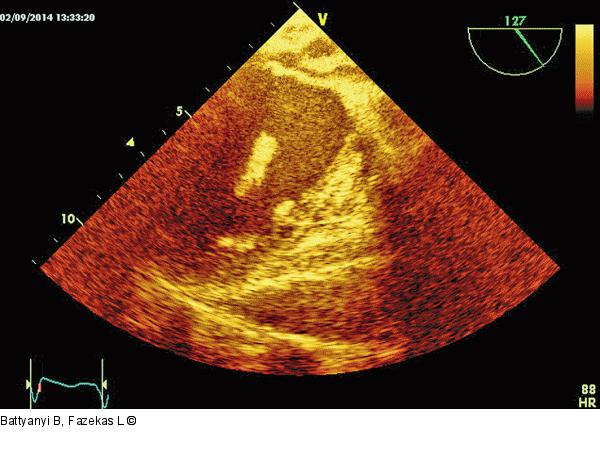

Abbildung 8: Thromboembolus

Thromboembolus in der Mitte der linken Kammer